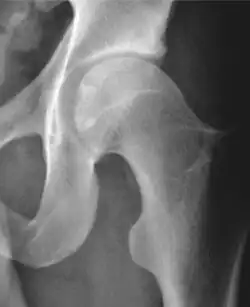

X-ray

Projectional radiography ("X-ray") is often considered first line for FAI.[10] Anterior-posterior pelvis and a lateral image of the hip in question should be attained.[10] A 45-degree Dunn view is also recommended.[10][19]

| Measurement | Image | Target | Normal value |

| Center-edge angle of Wiberg | ![]() |

The superior-lateral coverage of the femoral head. | |